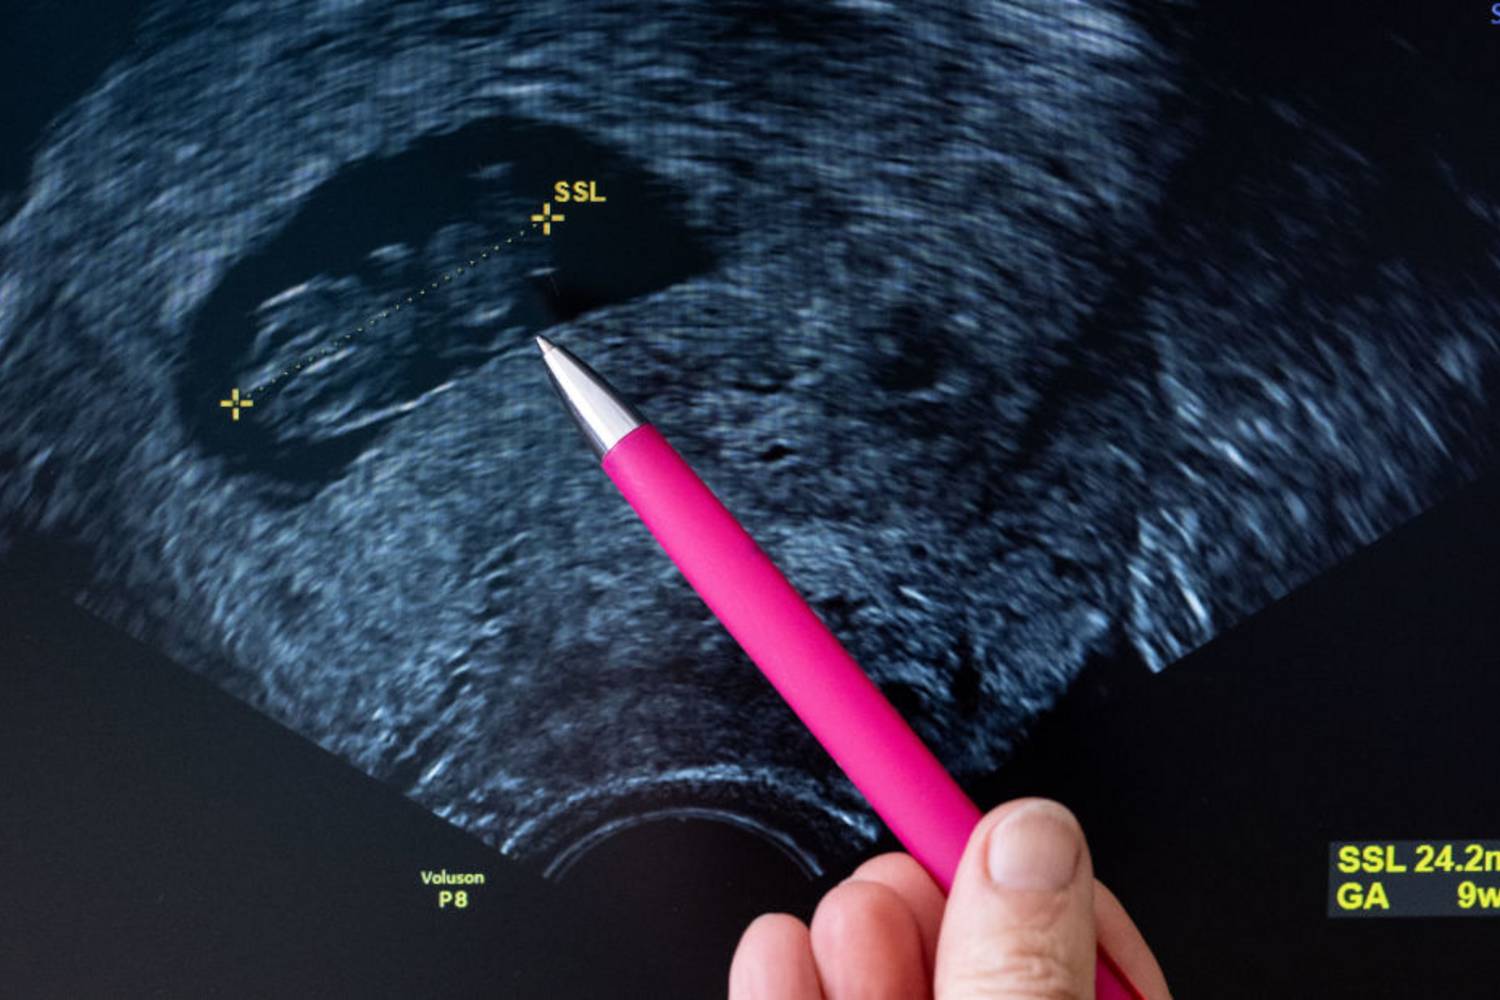

Mivel számos daganatos megbetegedés kockázata megnő a kor előrehaladtával, a nőknek rendkívül fontos a rendszeres fizikális és ultrahangos kismedencei vizsgálat és az úgynevezett rákszűrés, elsősorban a petefészek-, méhnyak- és méhtestrák korai jelei után kutatva. Ekkor nyílik alkalom arra is, hogy a páciensek kórtörténetét és családi egészségtörténetét megismerve a nőgyógyász felhívhassa a figyelmet az olyan örökölhető daganatos betegségekre, mint a petefészek-, a vastagbél- vagy az emlőrák.